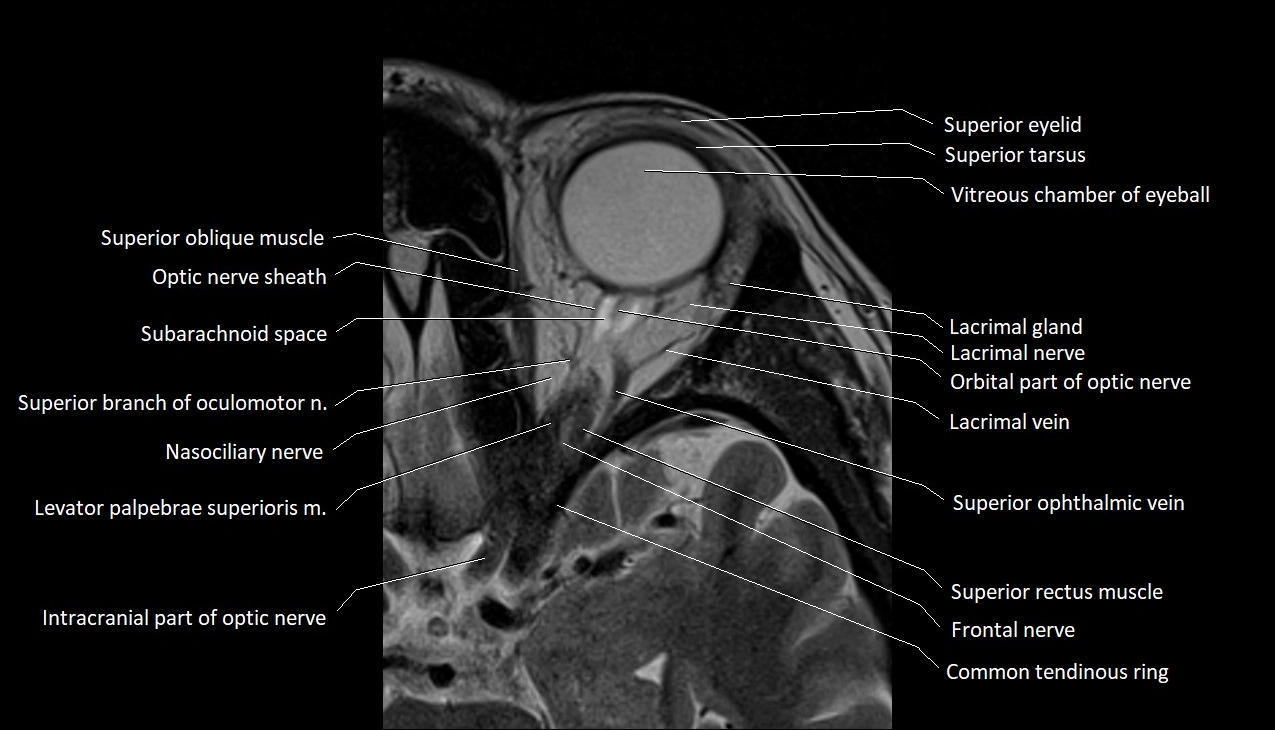

- Anterior chamber of eyeball

- Common tendinous ring (Annulus of zinn)

- Intracranial part of optic nerve

- Lacrimal gland

- Lacrimal nerve

- Lacrimal vein

- Levator palpebrae superioris muscle

- Optic nerve sheath

- Orbital part of optic nerve

- Subarachnoid space of optic nerve

- Superior eyelid

- Superior oblique muscle

- Superior ophthalmic vein

- Superior rectus muscle

- Superior tarsus

- Trochlear nerve (Cranial nerve IV)

- Vitreous chamber of eyeball